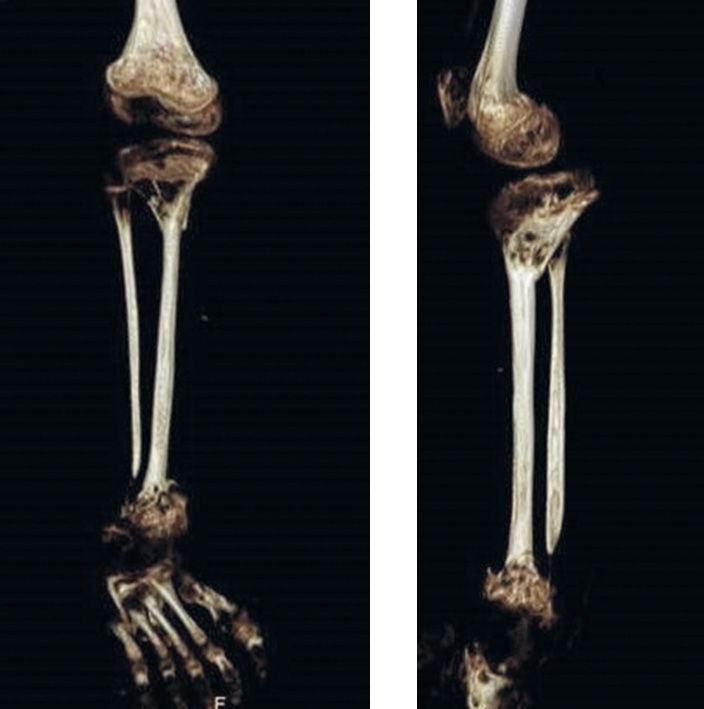

Fig. 6. Three-dimensional modeling of computed tomography slices after microsurgical transplantation to eliminate a defect in the right tibia bones

The integrity of the lower leg was restored approximately 1.5 years. After restoring the integrity of the tibia of the affected limb, the patient could walk with an orthosis for the entire lower limb, but without additional means of support, lead an active lifestyle with some restrictions and attend educational institutions. Limb shortening was compensated for by increasing the height of the sole of the orthopedic shoes.

At 1.5 years after autografting, the patient was diagnosed with multiplanar deformity of the femur, and the tibia on the lesion side, flexion–extension contracture of the right knee joint, valgus deformity of the distal metadiaphysis of the tibia on the donor side, and leg-length difference were reconstructed. Indications for stage 2 of the limb reconstruction were formulated.